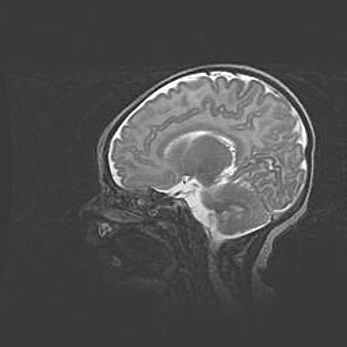

Неполная лизэнцефалия (пахигирия). Открытая гидроцефалия.

Возраст: 17 дней

Вес: 3110 г

Пол: мужской

Окружность головы: 33,5 см

Срок гестации: 35-36 недель

Лизэнцефалия—недоразвитие корковой пластинки и мозговых извилин в результате нарушения миграции нейронов коры. Поверхность мозговых полушарий гладкая. Микроскопически выявляется отсутствие нормальных слоев коры и скопление групп нейронов в подкорковом белом веществе.

Пахигирия—уменьшение числа вторичных извилин. В пораженном полушарии нервные клетки образуют толстый недифференцированный слой с неправильно расположенными нервными волокнами и группами гетеротопных клеток. Нервные клетки незрелые. Белое вещество истончено. При этом нередко аномально развит корково-спинномозговой путь.